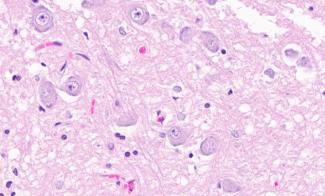

Brain cells under a microscope

LifeNet Health LifeSciences Human Biospecimens offers high-quality human brain and other neurological tissues recovered with the best practices in procurement by highly trained tissue recovery specialists. Tissues can be recovered from both non-diseased control donors and donors with medical conditions (i.e. Alzheimer’s Disease, TBI, PTSD).

LifeNet Health is able to recover and prepare neurological biospecimens for a variety of research including histological assessment, metabolic function, genomics, proteomics, and other novel applications. Scientists can utilize recovered cadaveric brain tissue for basic research, biomarker identification, diagnostic testing, and drug discovery, all of which have the potential for novel treatment modalities.